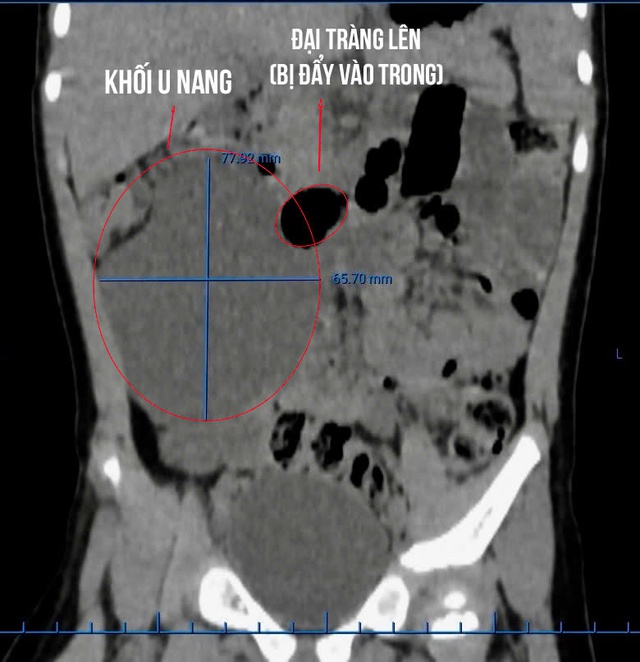

Kết quả siêu âm ổ bụng cho thấy, từ vùng hạ sườn phải xuống hố chậu phải xuất hiện một cấu trúc dạng nang kích thước lớn. Hình ảnh chụp CT scan xác định khối u nang chiếm gần nửa vùng bụng phải, đẩy toàn bộ các quai ruột sang bên trái.

Trong quá trình phẫu thuật, các bác sĩ xác định đây là khối u nang lớn nằm sau phúc mạc (phúc mạc còn gọi là màng bụng, là lớp màng bao phủ mặt trong thành bụng và bọc các cơ quan trong ổ bụng như gan, dạ dày, ruột…).

Khối u khiến toàn bộ đại tràng phải bị đẩy lệch vào giữa ổ bụng, nằm sát các cấu trúc quan trọng vùng sau phúc mạc như thận, niệu quản và bó mạch chậu phải. Ê-kíp phẫu thuật đã tiến hành bóc tách cẩn trọng, giải phóng các cấu trúc và cắt bỏ hoàn toàn khối u nang.